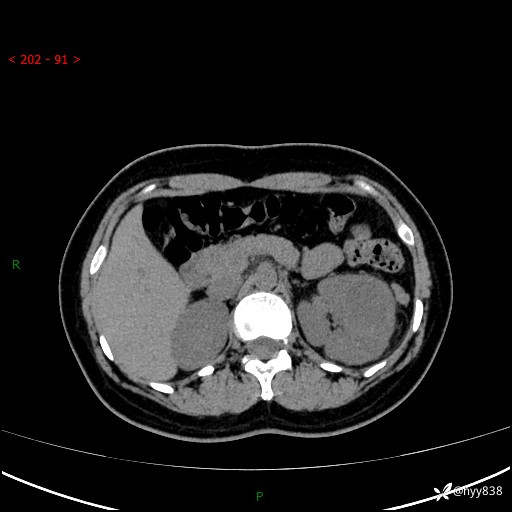

现病史:患者于1周前因左侧腰腹部间断胀痛不适,无恶心呕吐,无明显肉眼血尿,无畏寒发热,无尿频尿急,起病初,患者来我院就诊,查CT提示左肾低密度影,外周血提示:白细胞11.25*10^9/L.行抗感染治疗后未见明显好转,06-18泌尿系增强CT提示左肾类圆形低密度占位(脓肿?肿瘤?),大小:4.0*3.2cm,为求进一步治疗,门诊以“左肾占位”收住我科。 起病以来,患者精神佳,饮食、睡眠良好,大小便正常,体力体重无明显变化。

双肾CT平扫+增强